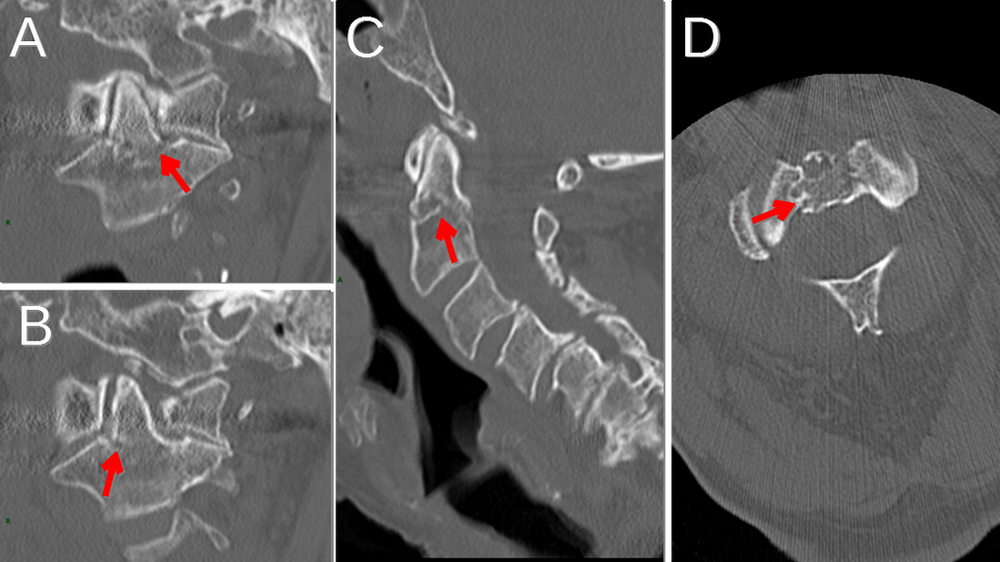

Current Concepts in the Management of Type II Odontoid Fractures What Is A Dens Fx We will briefly explain what a den's fracture is, how an odontoid fracture is diagnosed, different ways to treat a den's fracture, and what are the. Odontoid process fracture, also known as a peg or dens fracture, occurs where there is a fracture through the odontoid process. The odontoid process, known as the dens, is a bony element extending superiorly. What Is A Dens Fx.